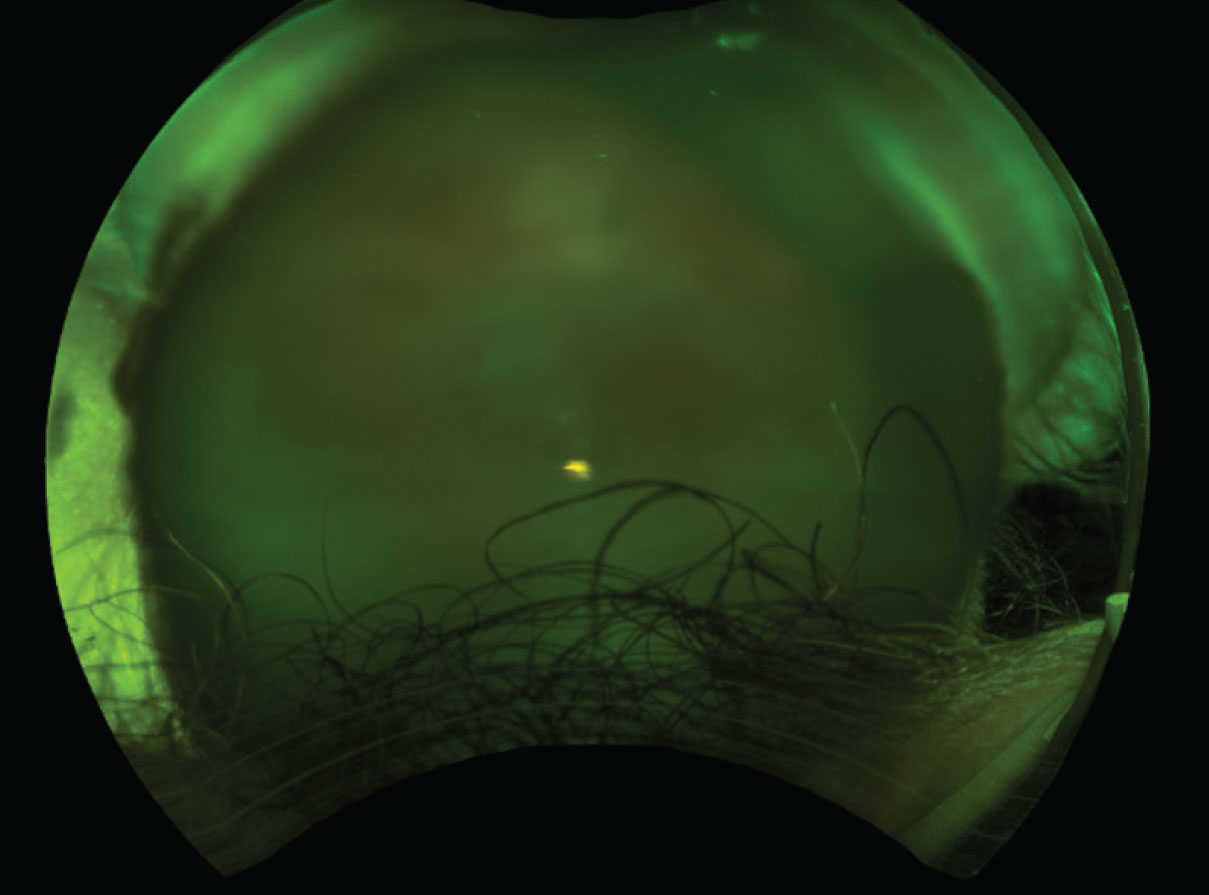

Slit lamp exam of the right eye was notable for 1+ flare in the anterior chamber and 2-3+ vitreous cell. The fundus exam showed multifocal yellow subretinal lesions (Figure 1). The left eye conjunctiva was injected, and the view into the anterior chamber and fundus was limited secondary to dense corneal neovascularization, diffuse stromal edema and corneal scarring. The vitreous was replaced by silicone oil, precluding effective ultrasonography (Figure 2).

Figure 2. Dense vitreous opacities in the left eye at the initial presentation caused this poor view of the fundus findings. Visual acuity was no light perception. |